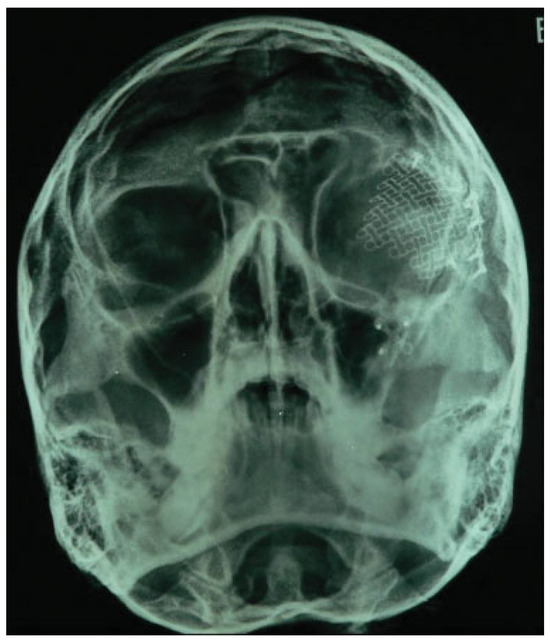

Titanium Mesh Reconstruction of Orbital Roof Fracture with Traumatic Encephalocele: A Case Report and Review of Literature

Case Report